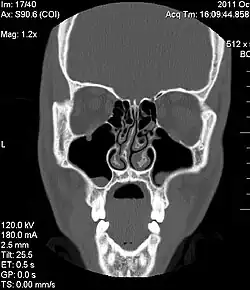

Ausgeprägte Septumdeviation, CT-Scan, in einer coronalen oder frontalen Schichtung

Die Diagnose einer Septumdeviation wird mittels äußerer Inspektion der Nase, vorderer Rhinoskopie, Endoskopie oder Computertomografie (CT) gestellt. Wie stark eine Septumdeviation die Nasenatmung behindert, kann mithilfe einer Rhinomanometrie gemessen werden. Außerdem sollte eine Riechprüfung durchgeführt werden.